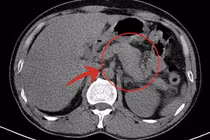

Bệnh nhân nữ, 40 tuổi, nhập Bệnh viện Đa khoa Hùng Vương trong tình trạng đau bụng vùng thượng vị và hạ sườn phải, kèm buồn nôn, chướng nhẹ. Qua thăm khám và siêu âm, các bác sĩ phát hiện sỏi túi mật lâu năm gây viêm túi mật cấp.

Kết quả khiến ai cũng bất ngờ: 130 viên sỏi với đủ kích thước đã được lấy ra từ túi mật của bệnh nhân. Sau phẫu thuật, bệnh nhân được chuyển về Khoa Ngoại để tiếp tục điều trị và theo dõi sức khỏe.

Hơn 130 viên sỏi trong túi mật bệnh nhân - Ảnh VCC

Bà D.T.N.T. nhập viện trong tình trạng đau dữ dội vùng hạ sườn phải, sốt cao và liên tục nôn ói. Kết quả chụp CT cho thấy viêm túi mật hoại tử, nhiễm trùng, bạch cầu tăng cao, buộc phải mổ cấp cứu.